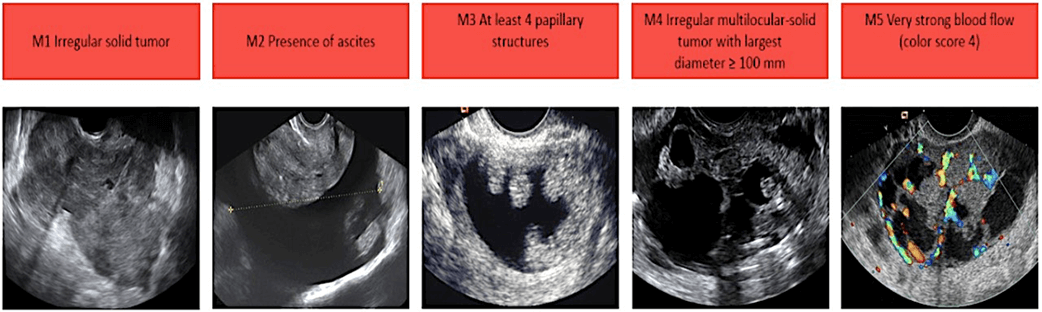

Features of Malignant Cancerous Ovarian Cysts:

Malignant Cancerous Ovarian Cysts